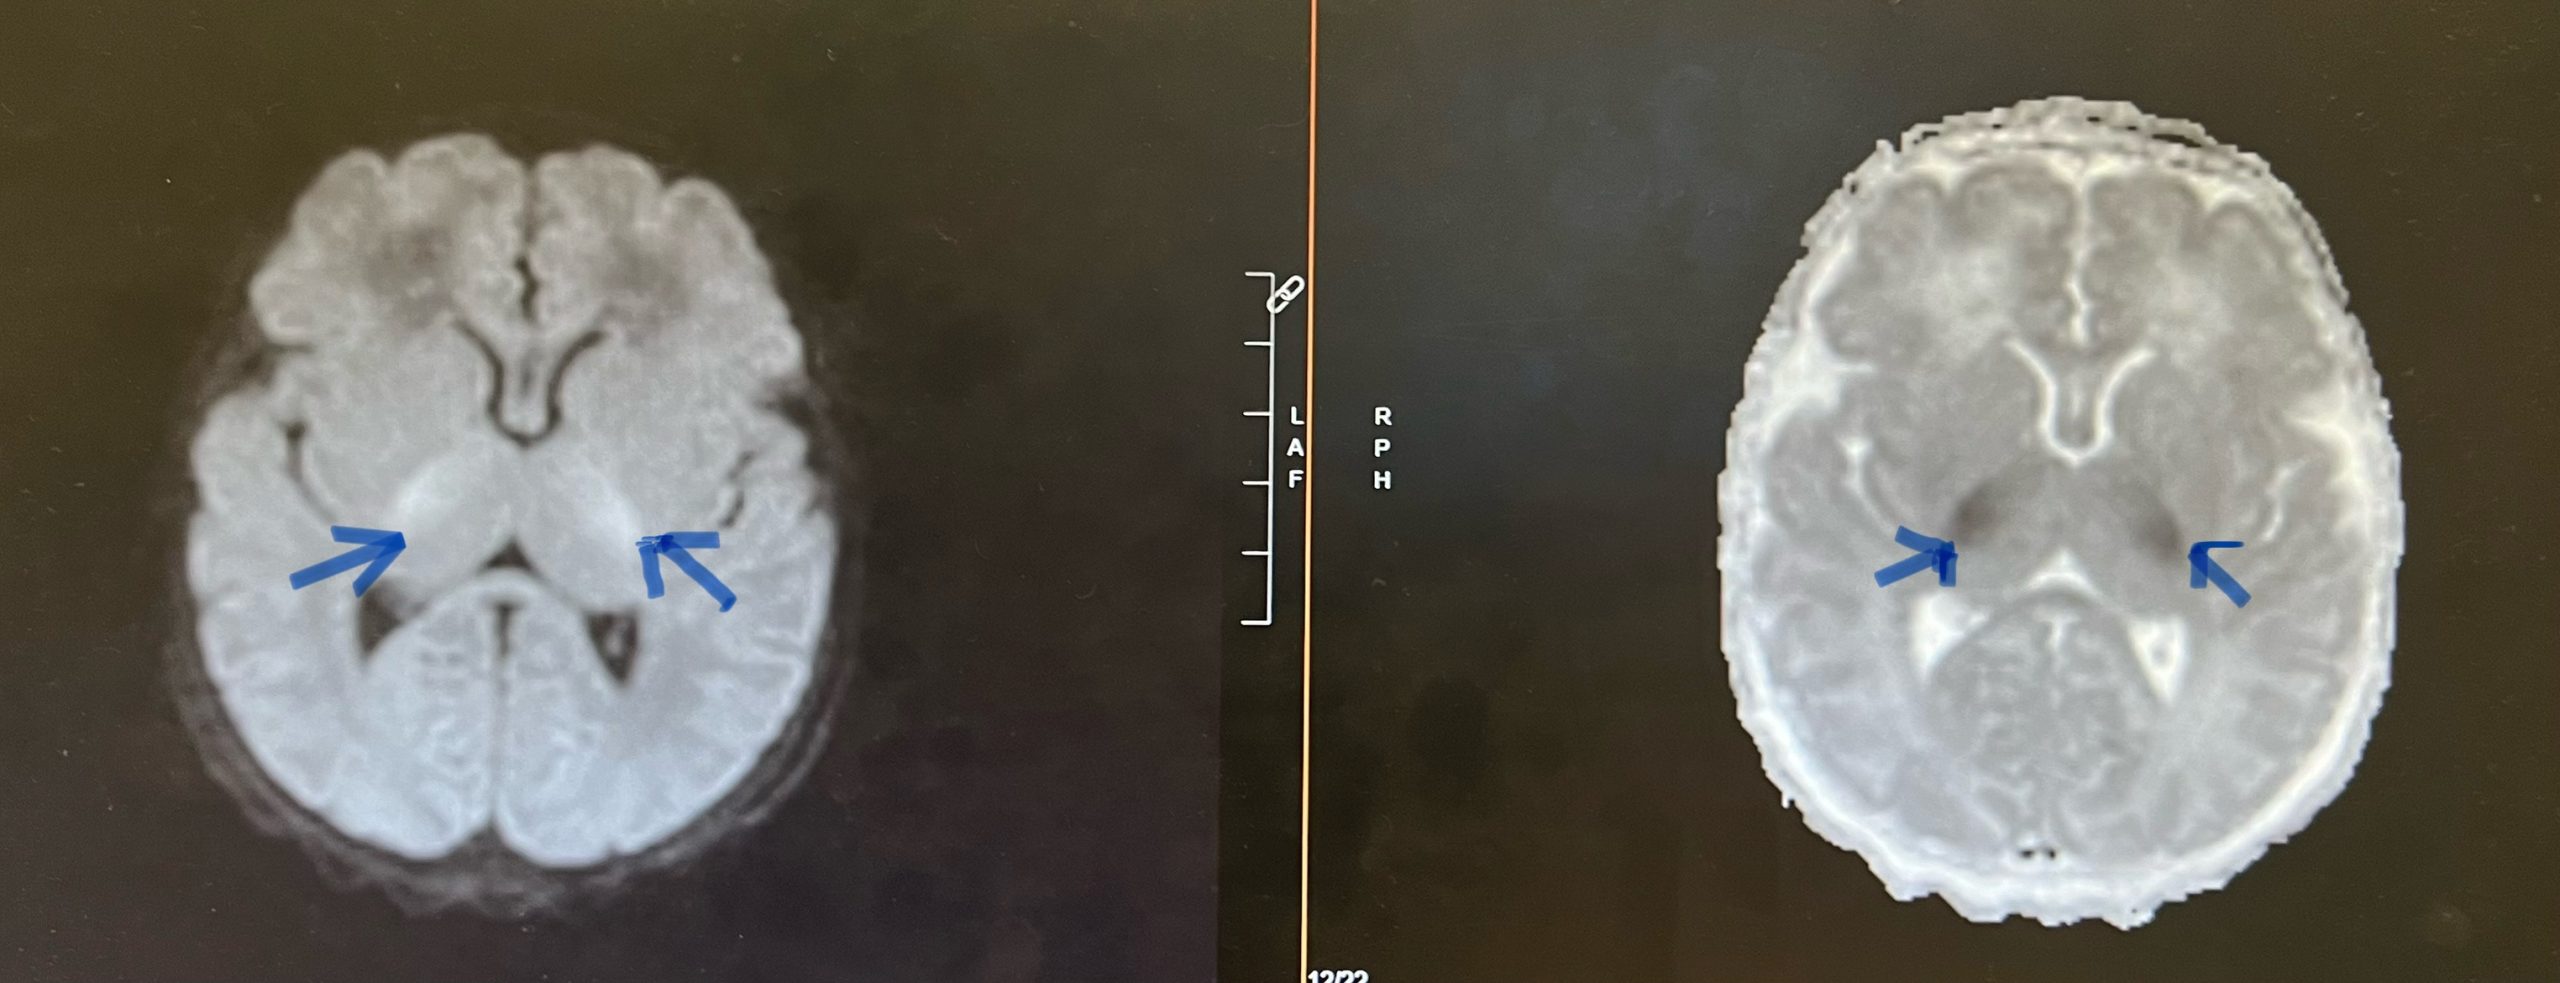

Case Presentation: A two-day old exclusively breastfed male born at term (no prior medical history; routine prenatal care) was discharged at 36 hours of life from the nursery, 5% down from birth weight. He had difficulty latching to feed post discharge and at 45 hours of life, presented to an outside emergency room in cardiorespiratory arrest.Pupils were fixed and dilated, and he was pulseless in the outside emergency room waiting area. He was resuscitated with return of spontaneous circulation. He was placed on an epinephrine infusion. Upon arrival to the Pediatric Intensive Care Unit, initial vital signs while on the epinephrine infusion were as follows: heart rate of 150, respiratory rate of 48, blood pressure of 96/81, and temperature of 98.7 degrees Fahrenheit.Initial glucose was “too low to read” and arterial blood gas only reported pH < 7. Echocardiogram showed severely depressed left ventricular function. Brain MRI showed diffusion restriction in the basal ganglia region suggestive of hypoxic ischemic encephalopathy. Sepsis workup was negative, lactic acid was 5.7 μmol/L, urinalysis with small ketones (10mg/dl), and acylcarnitine profile strongly suggestive of Medium-Chain Acyl-Coenzyme A Dehydrogenase Deficiency (MCADD). State Newborn Screen resulted on day 12 of life, indicative of MCADD-C8:17.7, C10:1.43, C8/C10: 12.37. Hypoglycemia panel genetic testing returned positive. Gene: acyl-Coenzyme A dehydrogenase (ACADM) variant: c.985A>G (p-Lys329Glu), zygosity: homozygous.